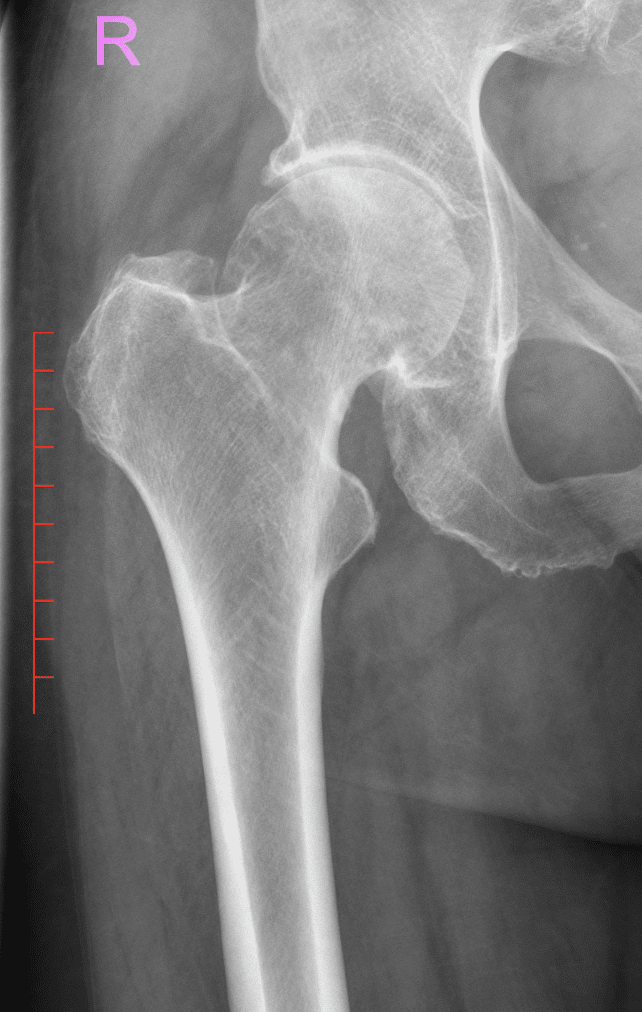

Hüftschmerzen zählen zu den häufigsten Beschwerden in der orthopädischen Praxis. Sie können infolge struktureller Veränderungen, etwa bei Hüftarthrose, oder durch funktionelle und traumatische Ursachen entstehen. Besonders häufig tritt ein Leistenschmerz auf, der sich beim Gehen, Aufstehen oder bei körperlicher Belastung bemerkbar macht.

Solche Beschwerden können auf strukturelle Veränderungen wie eine Hüftdysplasie oder ein Impingement-Syndrom (FAI) hinweisen, die nicht immer starke Schmerzen verursachen, aber langfristig zu Gelenkschäden führen können. Frühzeichen sind oft unspezifisch, etwa Rückenschmerzen durch Überlastung des Iliosakralgelenks oder Leistenbeschwerden am Tag nach dem Sport, die häufig fälschlich als Muskelzerrung oder Leistenbruch interpretiert werden.

Die Ursachen von Hüftschmerzen reichen von degenerativen Erkrankungen über strukturelle Engpässe bis hin zu akuten Verletzungen. Am häufigsten ist die Hüftarthrose, bei der sich der Gelenkknorpel langsam zurückbildet und oft von chronischem Leistenschmerz begleitet wird. Auch Fehlstellungen, muskuläre Dysbalancen, Impingement-Syndrome oder rheumatische Erkrankungen können Hüftschmerzen verursachen. Bei jüngeren Patient:innen stehen Überlastung oder sportbedingte Veränderungen der Hüftstruktur im Vordergrund.

- Degenerative Veränderungen: Knorpelabnutzung im Rahmen einer Hüftarthrose, häufig mit Leistenschmerz als Frühsymptom

- Strukturelle Ursachen: Engpassyndrome (Impingement), Gelenkfehlstellungen wie Hüftdysplasie oder Deformitäten – insbesondere das femoroazetabuläre Impingement (FAI), das Doz. Dr. Domayer während eines Fellowships im Children´s Hospital Boston, Harvard Medical School, sowie im Rahmen seiner Habilitation umfassend erforschte. Seine Expertise in der Diagnostik und Behandlung struktureller Veränderungen fließt heute direkt in die Versorgung seiner Patient:innen ein.